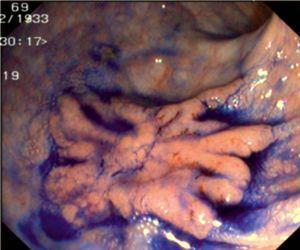

Fig. 3. Examples of flat lesions with conventional examination and after the application of indigo carmine 0.2-0.5%. a, b) Small flat adenoma, 3 mm in size. c, d) Large flat adenoma, 15 mm in size. e, f) Completely flat lesion (IIb in the Japanese classification). g, h) Depressed lesion, 3 mm in size) (IIc in the Japanese classification). I, J) Depressed lesion, 7 mm in size, histopathological study revealed submucosally invasive cancer (traditionally IIc in the Japanese classification, although recently such depressed lesions with a distinct central protrusion indicating submucosal invasion are termed IIc + Is). k, l) Flat elevated lesion with central depression, 10 mm in size, corresponding to a submucosally invasive cancer (IIa + IIc in the Japanese classification).